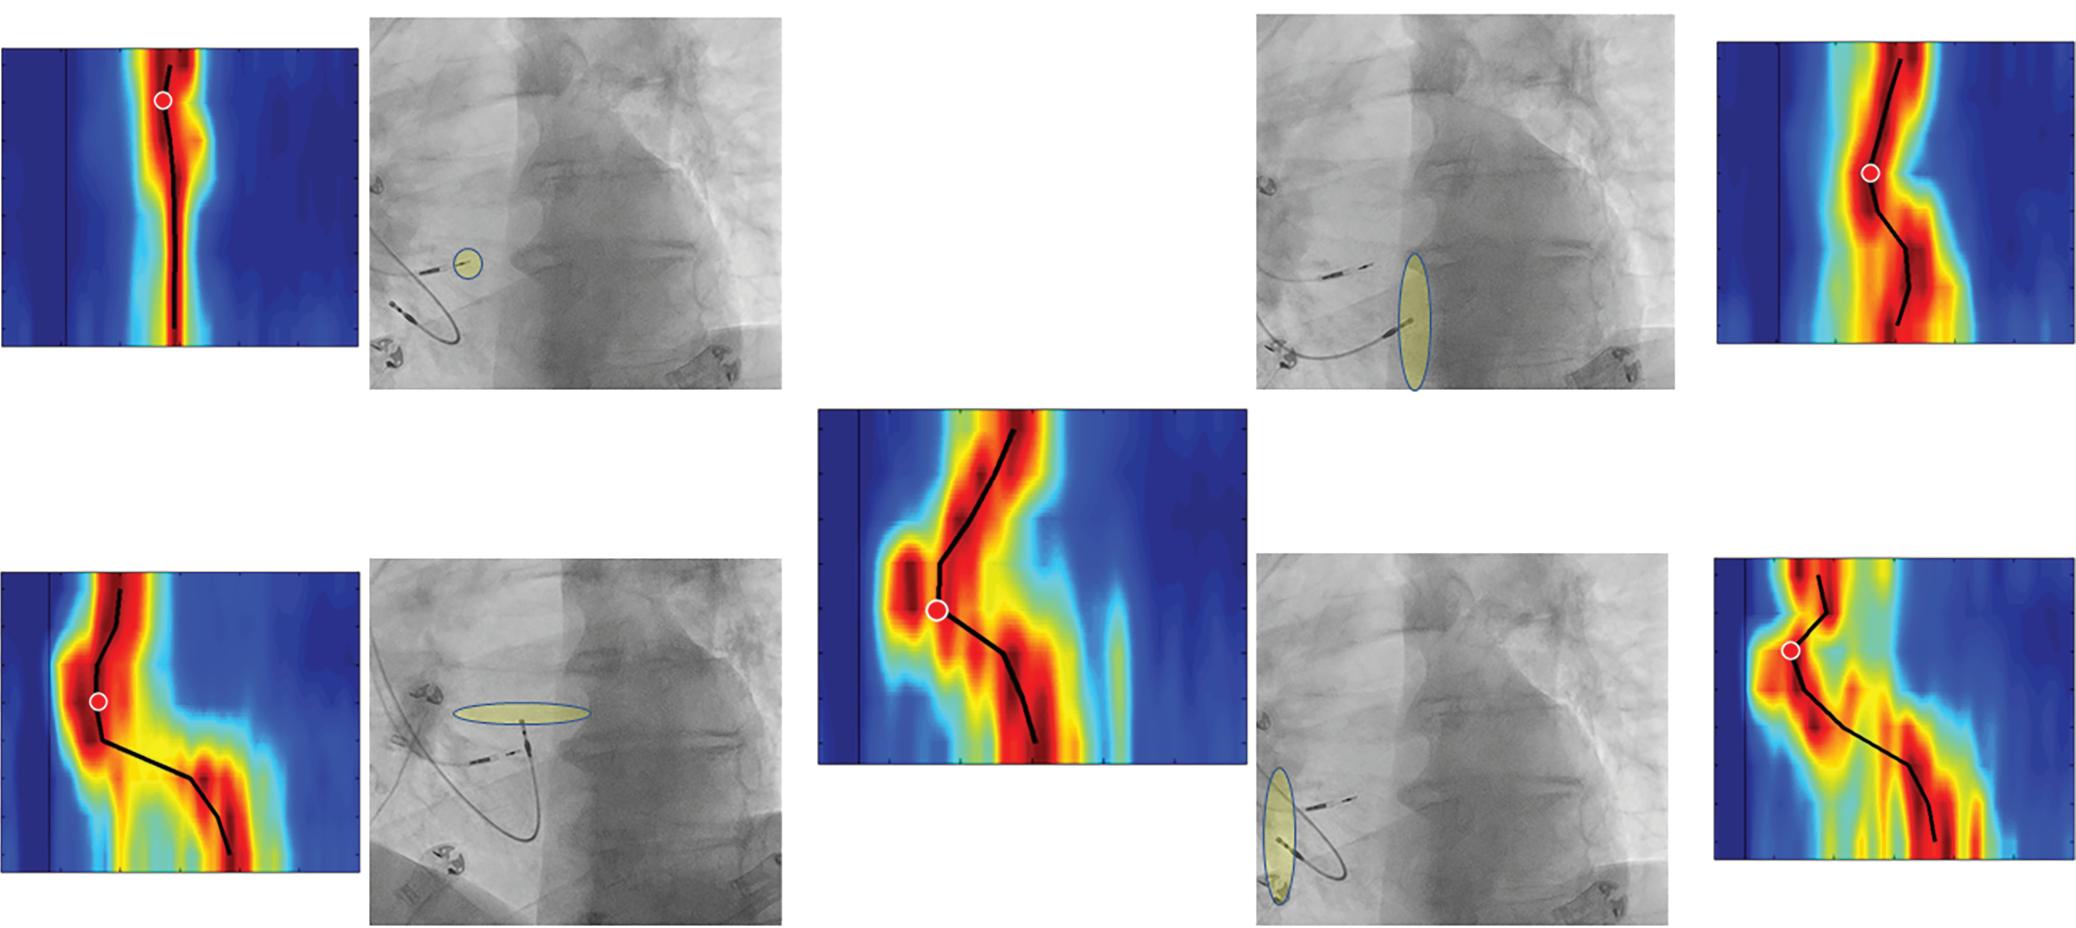

Figure 1: Ablation-induced Late Gadolinium Enhancement After Pulmonary Vein Isolation

Preprocedural LGE-MRI (1 day before PVI) Post-ablation LGE-MRI (3 months after PVI) LIPV RIPV LSPV RSPV LIPV RIPV LSPV RSPV Postero-anterior view Postero-anterior view

Left: 3D reconstruction of the LA with colour-coding based on image intensity ratios with thresholds for dense scar (red >1.32) and border zone (yellow 1.2–1.32), using ADAS 3D software (Adas3D Medical). Blue lines indicate the plane of the LA slices on the right. Middle: Overlay of the T1-weighted images with the LGE colour-coding described above. White arrows point to local ablation-induced LGE lesions. Right: T1-weighted LGE-MRI slice depicting the LA with evident LGE of PV ostial walls. LA = left atrium; LAA = left atrial appendage; LGE = late gadolinium enhancement; LIPV = left inferior pulmonary vein; LSPV = left superior pulmonary vein; PV = pulmonary vein; PVI = pulmonary vein isolation; RIPV = right inferior pulmonary vein; RSPV = right superior pulmonary vein.

facilitates discrimination from healthy tissue by LGE-MRI. Thus, even before validation of LGE-MRI for the detection of native atrial fibrosis, it was successfully employed for the assessment of atrial ablation-induced scarring (Figure 1).40,64,67